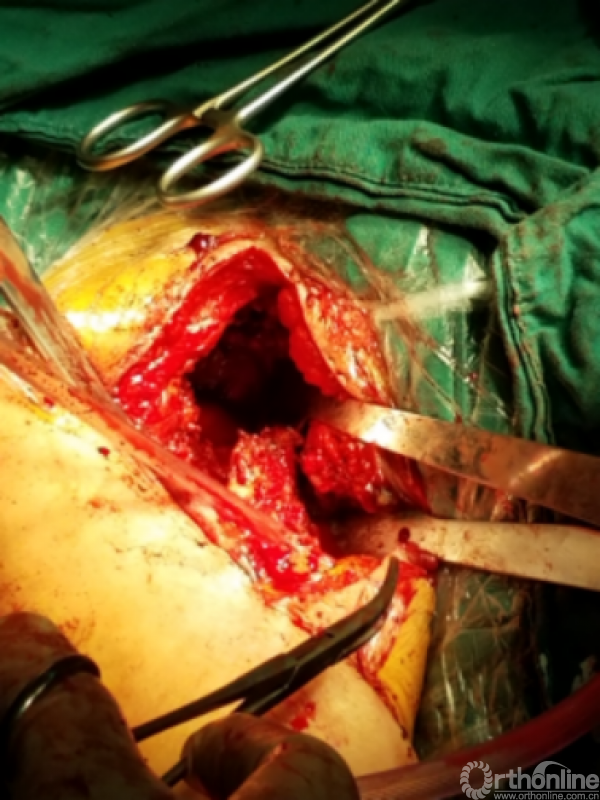

安尔碘溶液反复冲洗1000毫升,浸泡!!!

1.关节盂正常结构消失,前倾增大。

2.紧贴喙突内侧

3.骨质菲薄

4.特别小心肌皮神经及腋鞘

骨质疏松明显,皮质成虫蚀样改变,外侧缺损。

1.抗生素骨水泥占位器植入

2.不锈钢克氏针+抗生素骨水泥

3.柄部没有骨水泥,利于引流,头部较原有假体头部偏大,减少挛缩,占位关节腔,颈干角及后倾维持

4.用肌腱缝线固定减少排斥

5.后内侧结构尽量不去干扰,防止出现神经血管损伤。